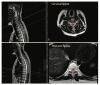

Spinal cord injury (SCI) often causes loss of sensory and motor function resulting in a significant reduction in quality of life for patients. Currently, no therapies are available that can repair spinal cord tissue. After the primary SCI, an acute inflammatory response induces further tissue damage in a process known as secondary injury. Targeting secondary injury to prevent additional tissue damage during the acute and subacute phases of SCI represents a promising strategy to improve patient outcomes. Here, we review clinical trials of neuroprotective therapeutics expected to mitigate secondary injury, focusing primarily on those in the last decade. The strategies discussed are broadly categorized as acute-phase procedural/surgical interventions, systemically delivered pharmacological agents, and cell-based therapies. In addition, we summarize the potential for combinatorial therapies and considerations.